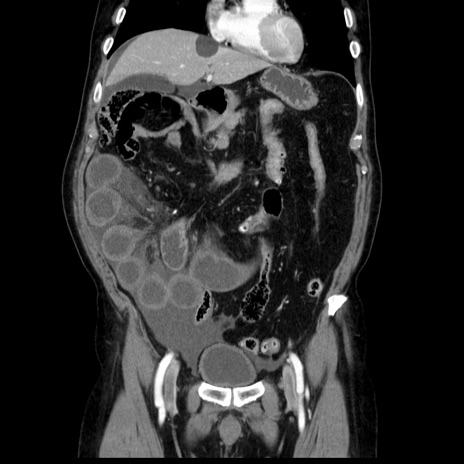

症例30(冠状断像)

【症例】80歳代男性

【主訴】臍周囲痛

【現病歴】約6時間前から臍下部痛が出現。次第に腹部膨隆・背部痛も生じてきたため来院。背部痛の場所は変化しない。

【身体所見】意識清明、BT 36.3℃、BP  131/87mmHg、P 87bpm、SpO2 100%(RA)、臍周囲自発痛・圧痛あり、反跳痛なし、自発痛部位に一致して板状硬あり、腹部膨隆、腸雑音減弱、CVA tenderness両側陰性。

【データ】WBC 19600、CRP 0.33